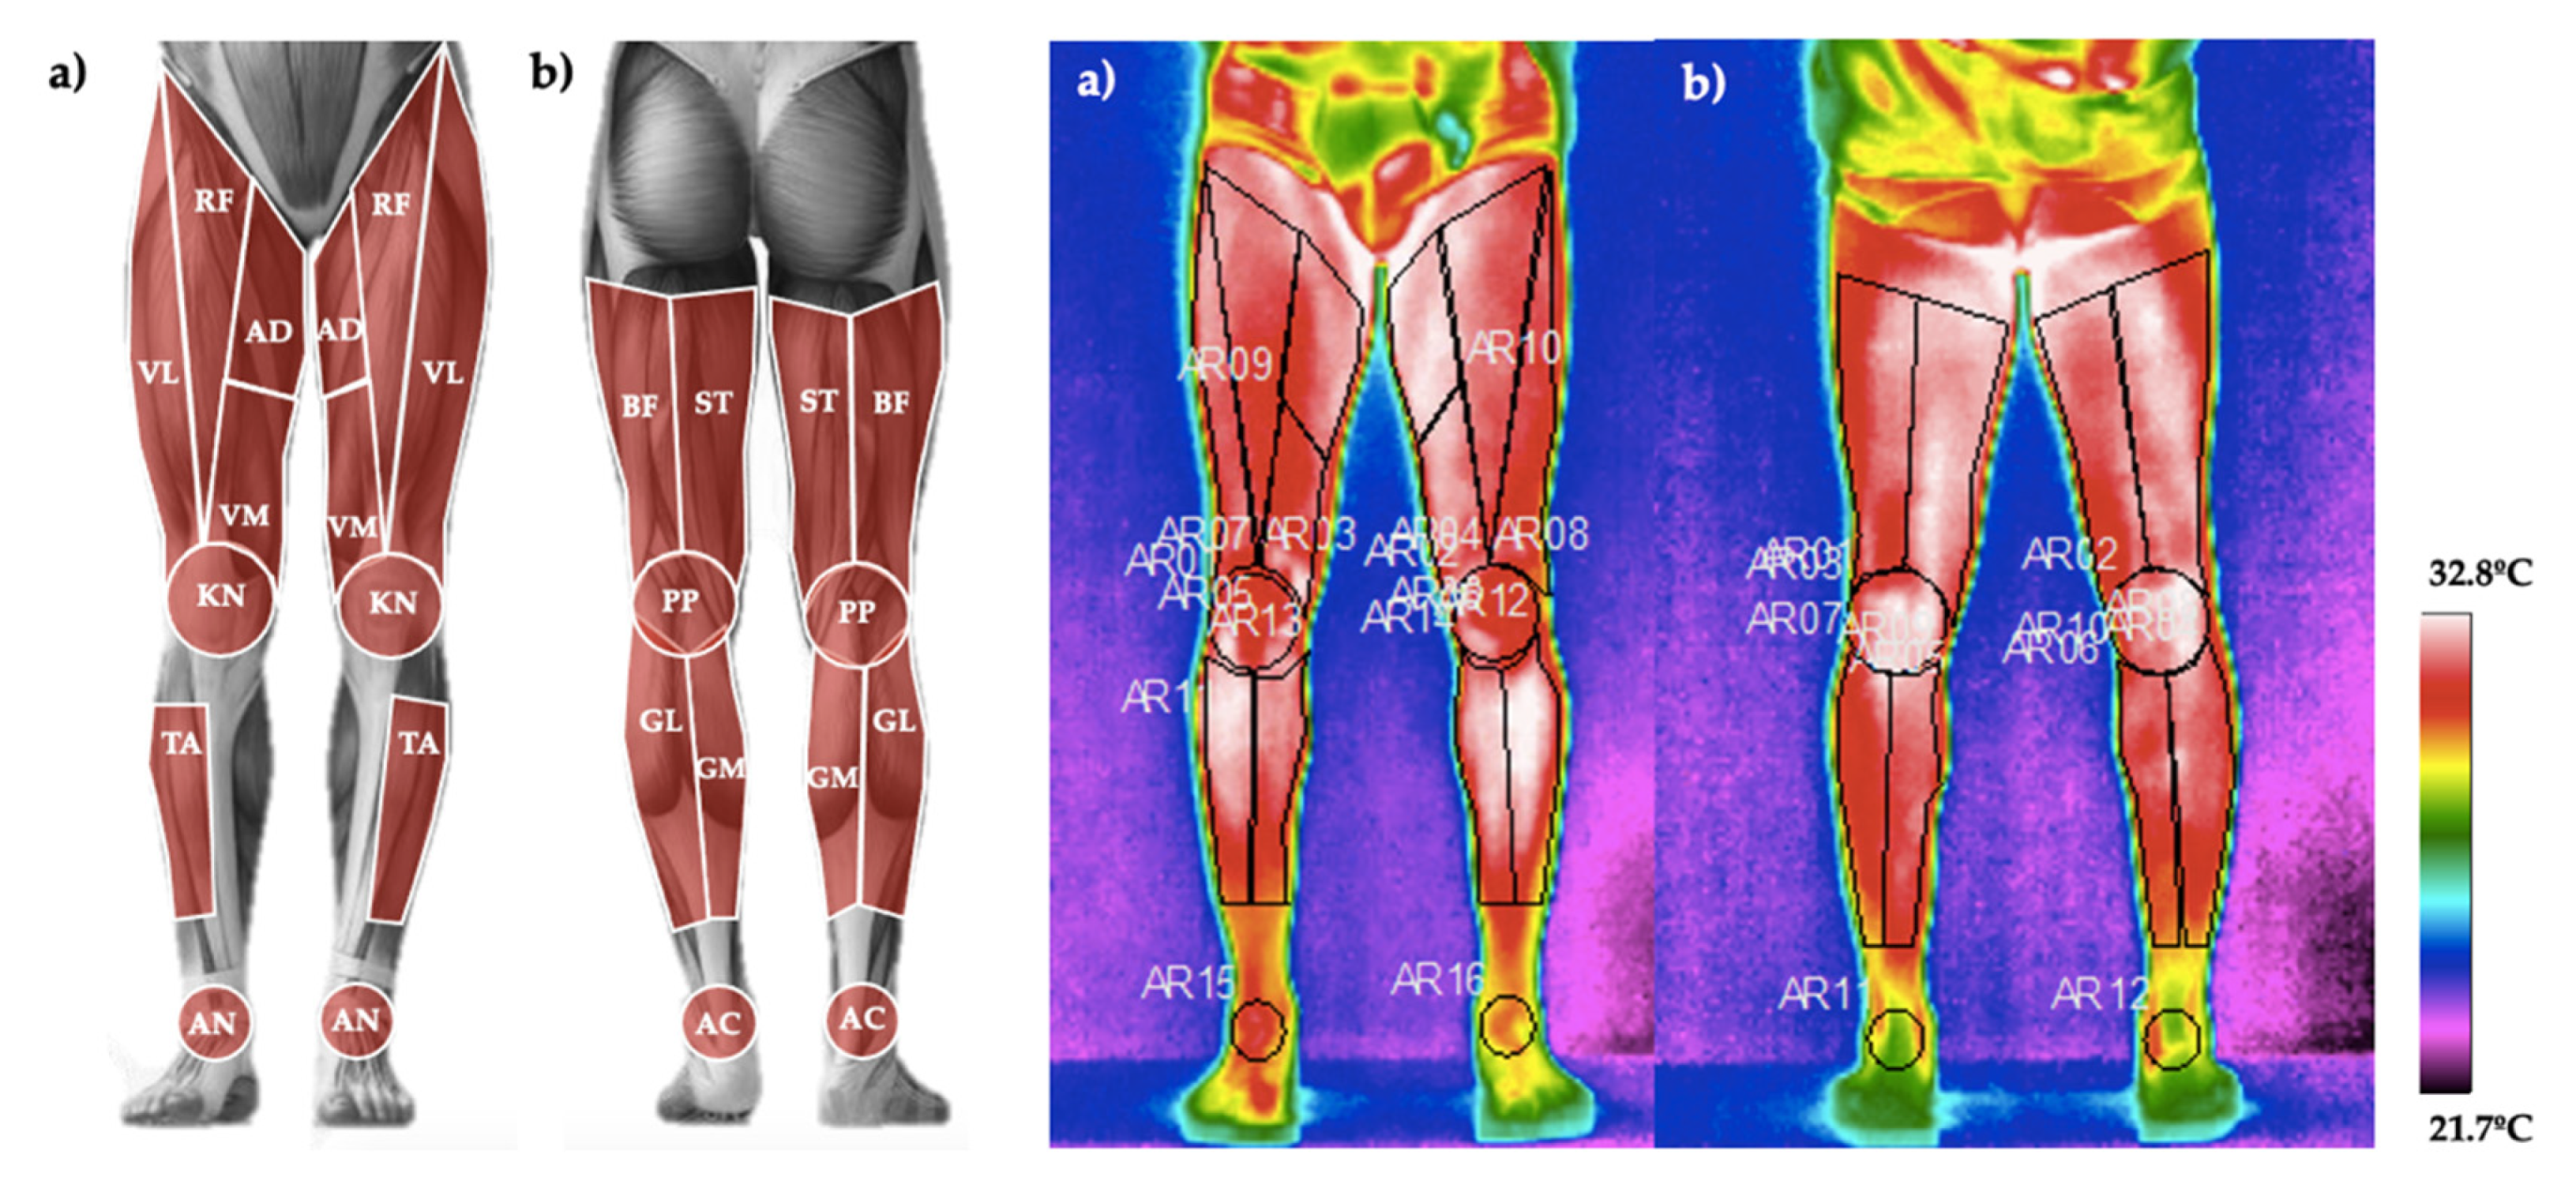

2.3.2. Skin Temperature